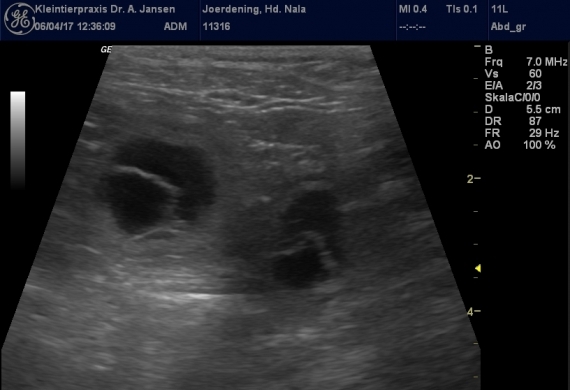

8. Woche der Trächtigkeit läuft (langsam)

Also die Trächtigkeit läuft "in vollem Umfang", heißt die Welpenbewegungen sind nun herrlich am entspannten Bauch zu spüren und Nalas Bauchumfang ist auf 88 cm angewachsen. Mit "langsam" ist nur Nalas Tempo bei Spaziergängen seit dieser Woche gemeint :) Wir hängen heute hier rum - denn die große Wäsche als Ausstattung für [...]